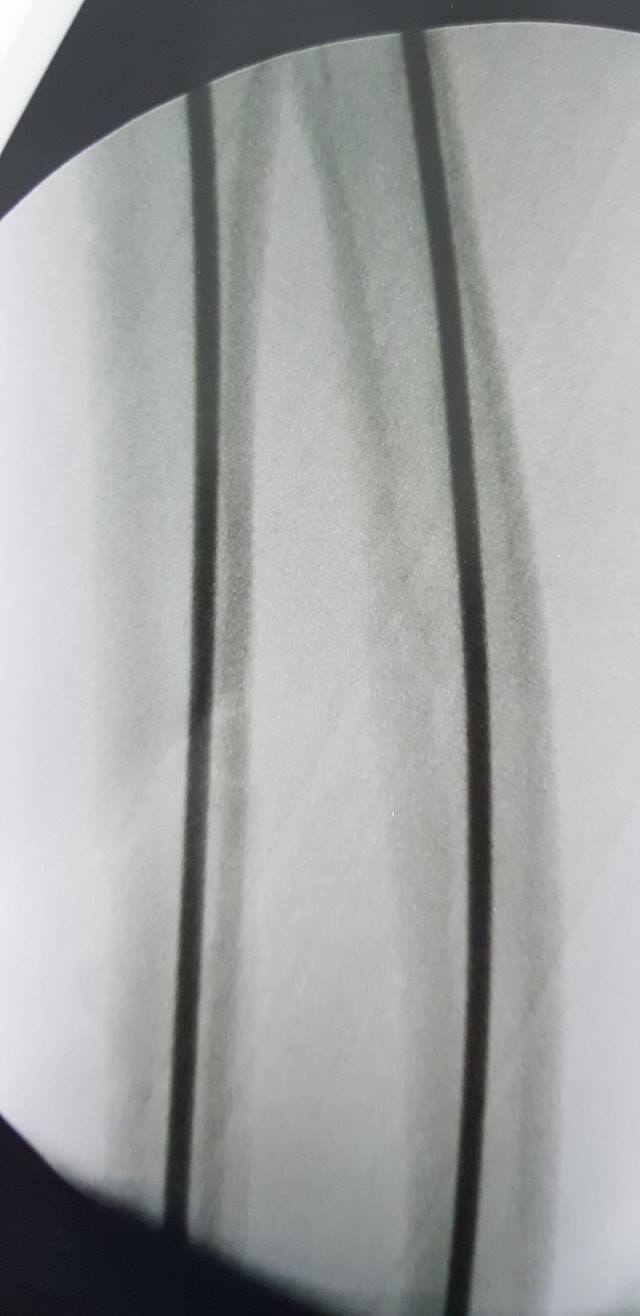

كافة انواع الكسور وعلاجها